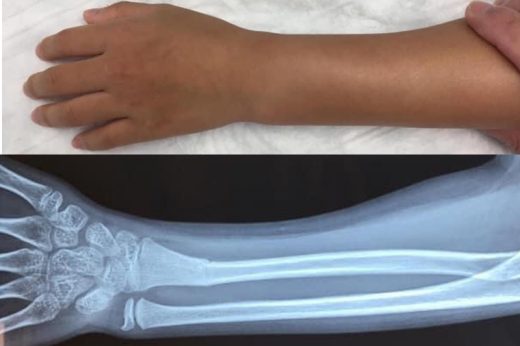

兒童骨骼較柔軟且有較厚的骨膜,骨裂多為嫩樹枝狀骨折(greenstick fracture),即骨頭部分斷裂但未完全斷開,癒合速度快,但若生長板受損需特別注意。